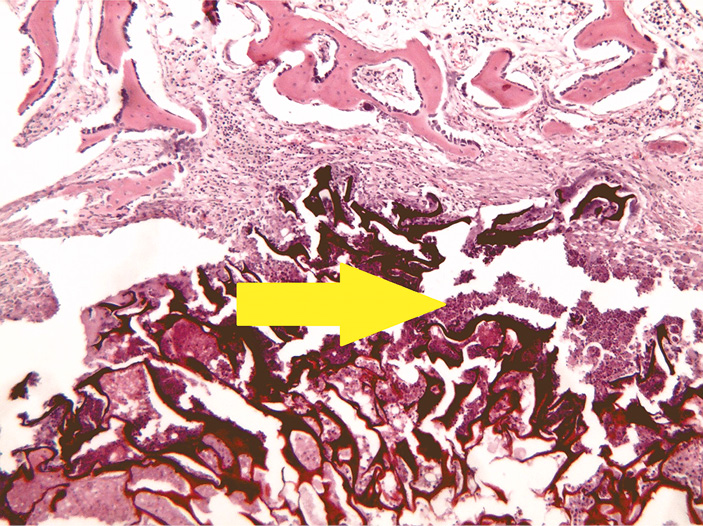

- Группа с губчатым материалом на основе хитозана (рис. 4).

Рис. 4. Группа с хитозаном: разрастание по краям дефекта ретикулофиброзной костной ткани. Окраска гематоксилином и эозином, увеличение ×40

На 28-е сутки в зоне дефекта отмечается участок, заполненный волокнистым хрящом. Элементов исследуемого образца синтетического материала в зоне дефекта не обнаружено. По краям дефекта кости виден переход волокнистой хрящевой ткани в ретикулофиброзную костную ткань.